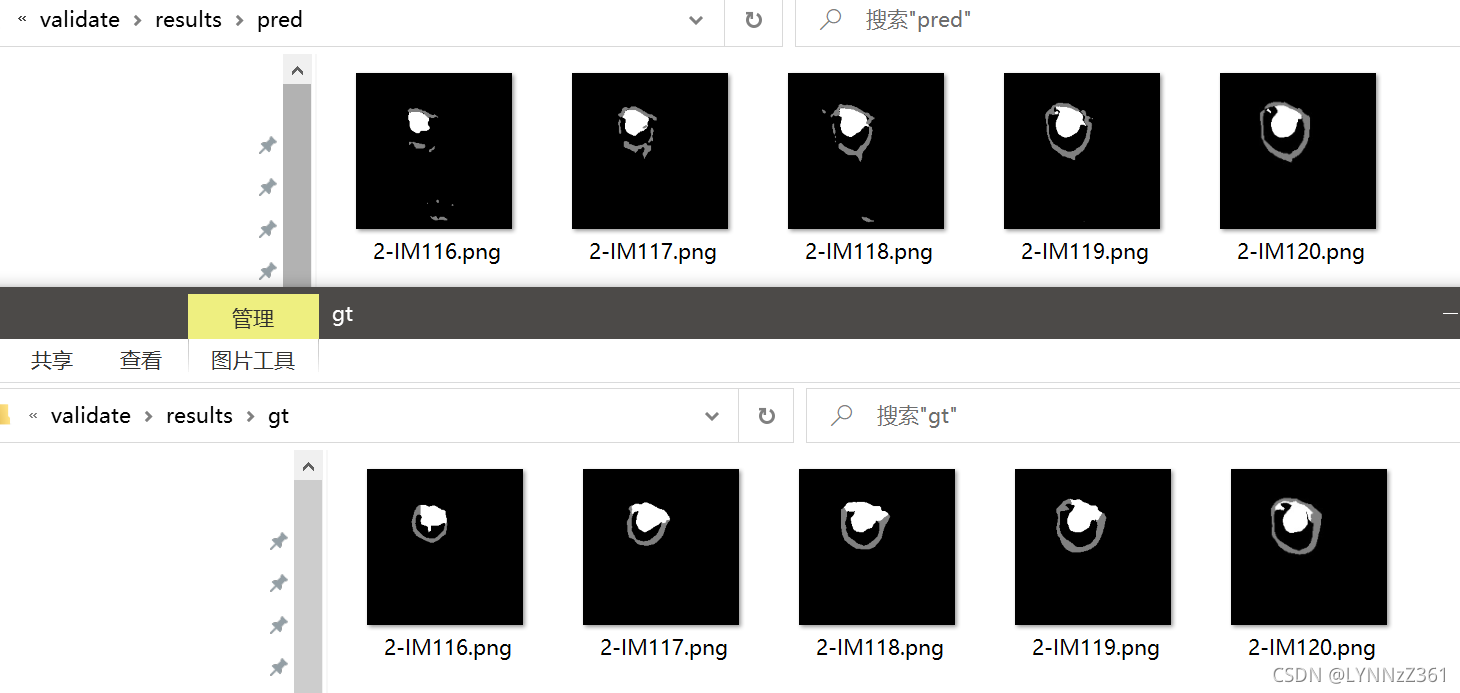

虽然我们的U-Net只用了24张图进行训练,但从结果可以看到,模型也能大致分割出目标。